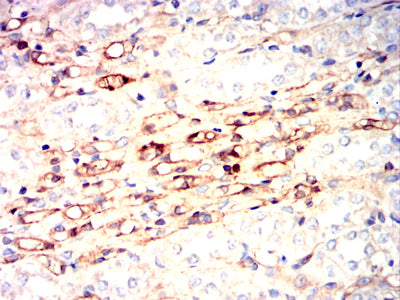

- Immunohistochemical analysis of paraffin-embedded human bladder cancer tissues using NPM3 mouse mAb with DAB staining.

- Immunohistochemical analysis of paraffin-embedded human rectum cancer tissues using NPM3 mouse mAb with DAB staining.

- Immunohistochemical analysis of paraffin-embedded rabbit kidney tissues using NPM3 mouse mAb with DAB staining.